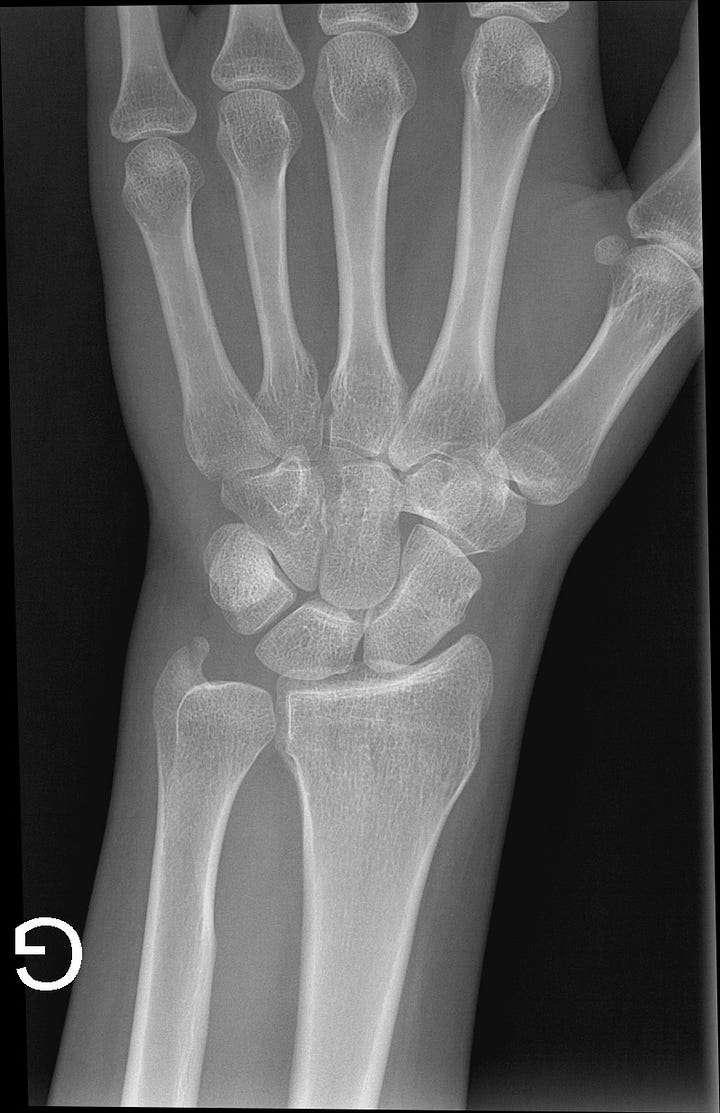

Sur les radios de mon poignet gauche, le médecin identifie deux fractures : une fracture de l’os capité et une fracture située à la pointe du radius.1

Ne me demandez pas de les situer, je n’ai pas compris non plus.